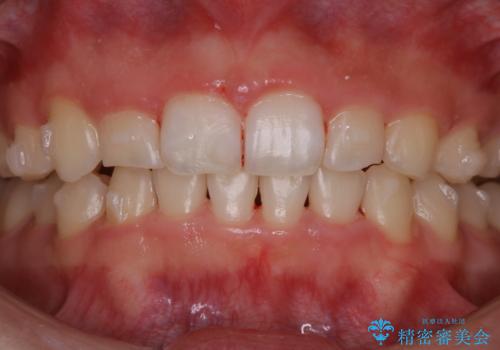

またPMTCを行うことで、ご自身本来の歯の色になり自然な明るさになります。

口元が自然な明るさになることで、より清潔感のある印象になるため結婚式・行事やイベント前などにもPMTCを行うはおすすめです。